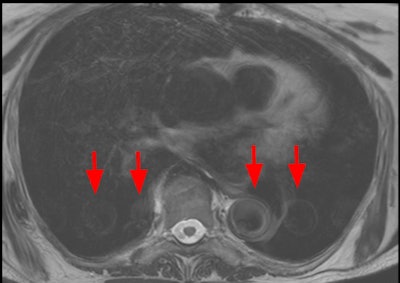

Dielectric effect, or standing wave effect, artifacts may be seen in cases of profuse ascites or in obese and pregnant patients, and it is due to the high magnetic field in a 3-tesla machine that can't maintain its homogeneity. Bright or dark "holes" in regions away from the receive coil caused by interference with the standing waves. These artifacts become more pronounced the larger the region of interest.

Dielectric artifact. Axial echo gradient fat-saturated T1-weighted slice of the abdomen acquired on a 3-tesla device, showing multiple blurred areas of signal loss (arrows) at distance of the receiving coil, in a patient with abundant ascites. The strategy in this case would be first to apply parallel radiofrequency transmission technique, and if insufficient, to rescan the patient on a 1.5-tesla scanner."Pregnant patients should always be explored at 1.5T," the authors pointed out. "Ascites can be handled by switching to a lower magnetic field device or drained before the exam. Parallel radiofrequency (RF) transmission or any other technology improving RF emission homogeneity will reduce dielectric effects (e.g., Philips' MultiTransmit, Siemens' TimTx, GE's MultiDrive, Canon's Multiphase Transmit).